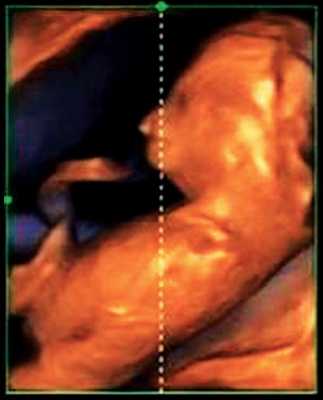

При эхографии в срок 13 недель 3 дня фетометрические параметры плода соответствовали гестационной норме, толщина воротникового пространства составила 1,5 мм; длина костей носа - по 2,5 мм. При трансвагинальном сканировании были обнаружены: затылочное энцефалоцеле размерами 7,4х3,5х3,7 мм (рис. 1), полидактилия кистей (рис. 2), увеличенные кистозно-измененные почки: правая - 28,5х21,3 мм; левая - 26,4х18,7 мм (рис. 3). Объем амниотической полости был нормальным для данного срока.

Синдром Меккеля. Диагностика и прогноз при синдроме Меккеля